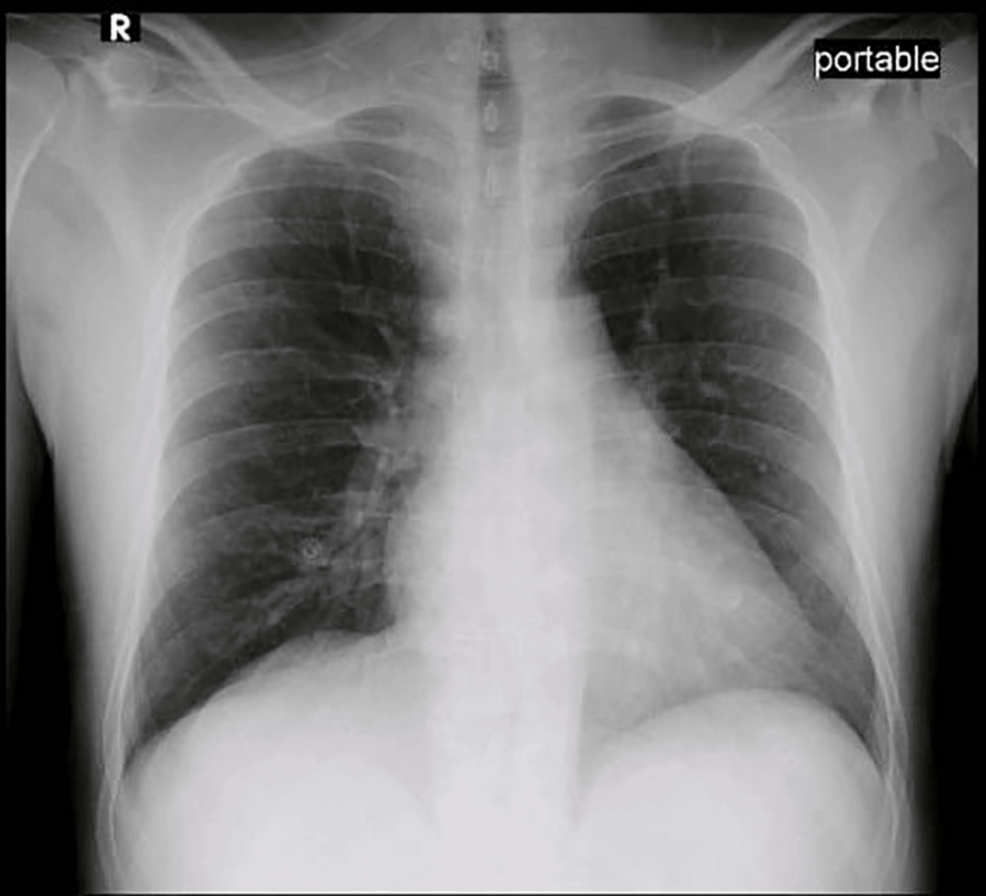

Imagine a scenario: a seemingly healthy child presents with unexplained fatigue and a bluish tinge to their skin, symptoms easily dismissed as a minor illness. But what if these subtle signs point to a growing, often overlooked health concern – methemoglobinemia triggered by common environmental exposures, exacerbated by underlying genetic predispositions? A recent case study involving a patient with Hemoglobin D trait and aniline exposure highlights a critical vulnerability, suggesting we may be on the cusp of recognizing a wider spectrum of ‘low-level’ methemoglobinemia cases with significant health implications. This isn’t just a rare genetic anomaly; it’s a potential public health issue demanding proactive investigation.

Methemoglobinemia occurs when the iron in hemoglobin is oxidized, rendering it unable to effectively carry oxygen. While traditionally associated with high doses of certain chemicals like aniline dyes, the case reported in Curet demonstrates that even relatively low levels of aniline exposure, combined with genetic factors like Hemoglobin D trait, can induce symptomatic methemoglobinemia. **Methemoglobinemia** itself isn’t new, but the increasing prevalence of aniline-based products in everyday life – from textiles and leather to hair dyes and even some industrial processes – raises concerns about chronic, low-dose exposure.

The Hemoglobin D trait further complicates the picture. This genetic variant affects the stability of hemoglobin, making individuals more susceptible to methemoglobin formation. The combination of genetic predisposition and environmental exposure creates a synergistic effect, lowering the threshold for symptomatic disease. This case underscores the importance of considering genetic factors when evaluating patients presenting with unexplained cyanosis or hypoxia.

Currently, methemoglobinemia is often diagnosed when levels are significantly elevated. However, the Curet case suggests that symptomatic cases can occur at lower methemoglobin levels, particularly in genetically predisposed individuals. This necessitates a recalibration of diagnostic thresholds and a greater awareness among clinicians. We can anticipate a shift towards more sensitive diagnostic testing and a broader consideration of methemoglobinemia in the differential diagnosis of patients presenting with ambiguous symptoms.